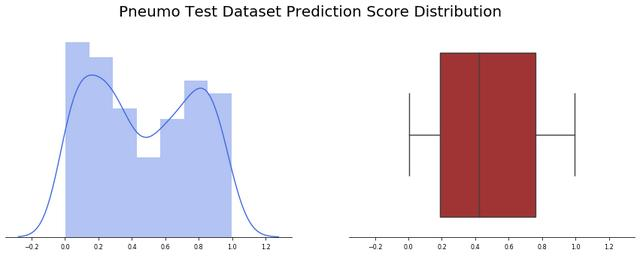

我们观察了234张诊断为正常的“未公开”图片(还有390张不是由Covid-19引起的肺炎)。应用批处理函数,我们观察到24幅图像出现假阳性(约10%)。让我们看看模型输出值是如何分布的,记住函数返回的值计算如下:

pred = new_model.predict(image)pred_pos = round(pred[0][0] * 100)

我们观察到,预测精度的平均值为0.15,并且非常集中于接近于零的值(中值仅为0.043),有趣的是,大多数误报率接近0.5,少数异常值高于0.6。

我们对390张标记为非Covid-19引起的肺炎的图像应用批测试功能,我们发现总共390张图片中只有3张出现假阳性(约0.8%),此外预测精度值的平均值为0.04,并且非常集中于接近于零的值(中值仅为0.02)。

总的结果甚至比以前的模型所观察到的还要好,有趣的是,几乎所有的结果都在前3个四分位之内,只有很少的异常值有超过20%的误差。